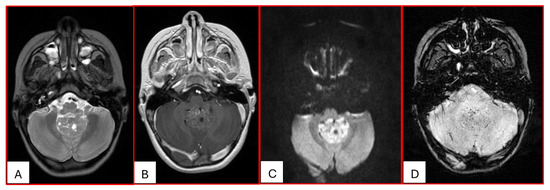

Since their first description by Rorke in 1995, the histogenesis of ATRTs has remained an enigma. Due to the expression of neural, epithelial, and mesenchymal markers, they likely derive from pluripotent fetal cells. Based on genetic and DNA methylation status and transcriptome profiles, ATRTs are further divided into three distinct molecular subgroups: ATRT-SHH, ATRT-TYR, and ATRT-MYC; further subclassifications have also been proposed. The WHO Classification of CNS tumors has included ATRTs in “Embryonal Tumors”. ATRTs are distinct from other embryonal tumors in their clinical presentation, tumor location, imaging characteristics, and prognosis. ATRTs often represent a surgical challenge as treatment requires removing a deep-seated large vascular mass from young patients. They are often resistant to conventional chemotherapy. Radiation therapy, which is imperative, raises serious concerns with regard to effects on the developing CNS of young patients. Safe and effective therapeutic measures are urgently needed.